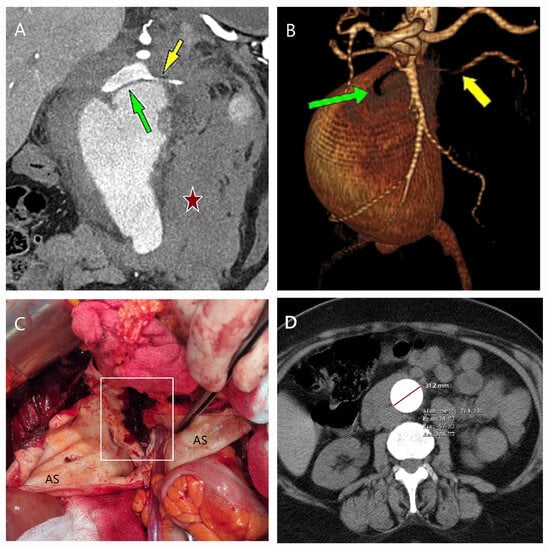

5.1. Failure of EVAR

5.2. Conversion to Open Surgery